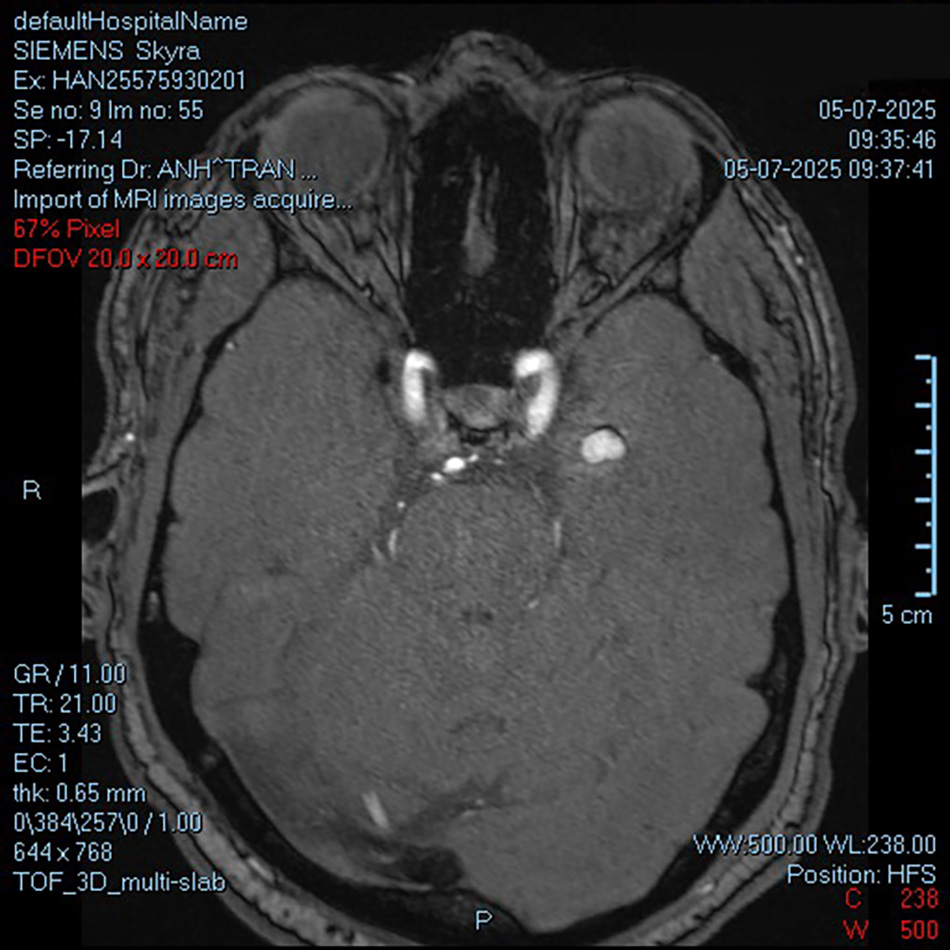

Hình ảnh MRI khối u mạch máu 9x14mm nhưng lại “ẩn mình” tại vị trí vô cùng nhạy cảm, sâu tới 5cm trong lớp vỏ não

Khối u tuy chỉ 9x14mm nhưng lại “ẩn mình” sâu tới 5cm trong lớp vỏ não – vị trí vô cùng nhạy cảm. Chỉ một sai lệch nhỏ trong thao tác có thể gây tổn thương nghiêm trọng cho vùng não xung quanh. Đây chính là thách thức lớn nhất của ca mổ: làm sao tìm đúng “tọa độ” khối u và loại bỏ nó mà không phá hủy những mô não khỏe mạnh phụ trách về khả năng ghi nhớ của người bệnh.